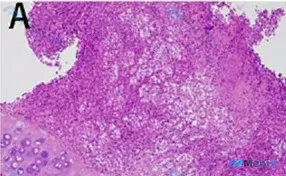

整理了一份有意思的TBLB(经支气管肺活检)病理读片思路,一起看看👇 --- 【基础信息与标本背景】 - 标本类型:经支气管肺活检(TBLB) - 主要镜下描述:非典型细胞浸润 + 淋巴细胞浸润 - 补充HE形态细节(结合读片):左下方可见残留的成熟软骨组织(软骨陷窝、同源群分布);右侧及上方为细胞...